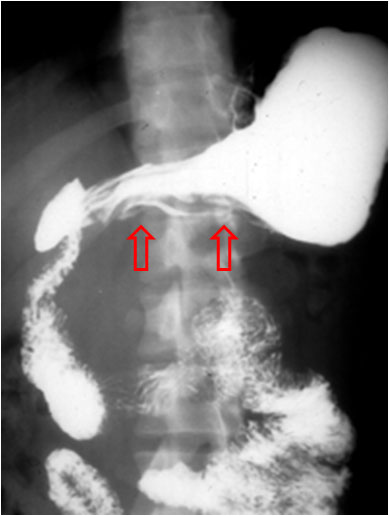

SIGNO DEL MOLDE

Recibe este nombre el aspecto de la luz del yeyuno en el esprúe avanzado o no tratado, en el estudio de tránsito intestinal baritado. Los pliegues mucosos aparecen borrados y el bario que llena la luz del intestino adopta la forma de un tubo relleno de cera endurecida. Habitualmente se asocia a segmentación marcada e hipersecreción (que no están presentes en esta imagen, que es una fotografía localizada en fosa iliaca izquierda de un tránsito intestinal).

Otro paciente con esprúe avanzado mostrando este signo. La apariencia de las asas intestinales en la radiografía se ha equiparado también al aspecto de la pasta de dientes.

En la literatura médica no es infrecuente encontrar este signo con su nombre original en francés: moulage o Signo del moulage.